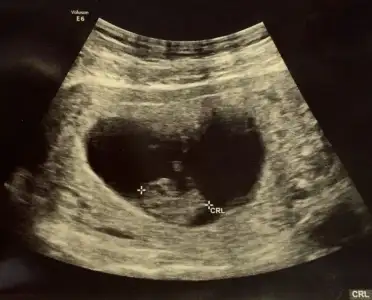

sandriyon tahminlerinizi alayım tatlımlar karından çekildim bugün çok fotojenik değil miyiz ama

ne guzel buyumus bebısler goruyoruz :) kız annesı :)Papatyamaviss bugun 9+1 günlüğüz kontrolden geldik.teyzesi bizede bi cinsiyet tahmininde bulunurmusun